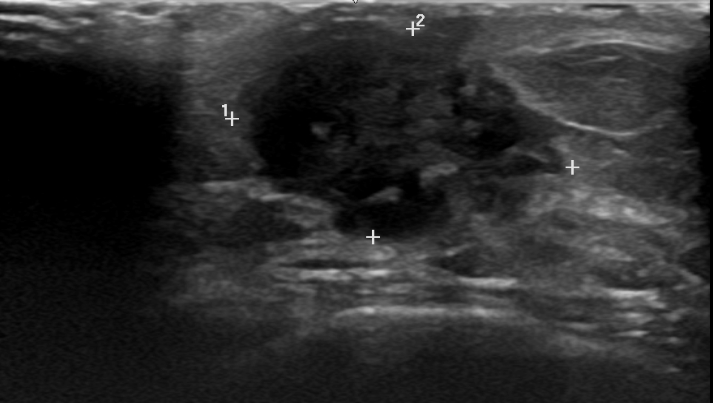

Paciente acude por múltiples motivos de consulta y el último de ellos refiere que quiere que le vean un bulto en el pecho que le ha sangrado.Hallazgos ecográficos

Se realiza una ecografía en centro de salud sobre lesión próxima a pezón de consistencia dura de más de dos dedos de grosor, donde se observa una imagen heterogénea (áreas isoecogénicas y áreas hipoecogénicas) sin captación de flujo de 20 mm o mayor, no aspecto ovoide sino masa circular. En axila próxima se observa ganglio ovalado con centro hiperecogénico sin captación de flujo que descarta adenopatía sospechosa de malignidad.Pruebas complementarias